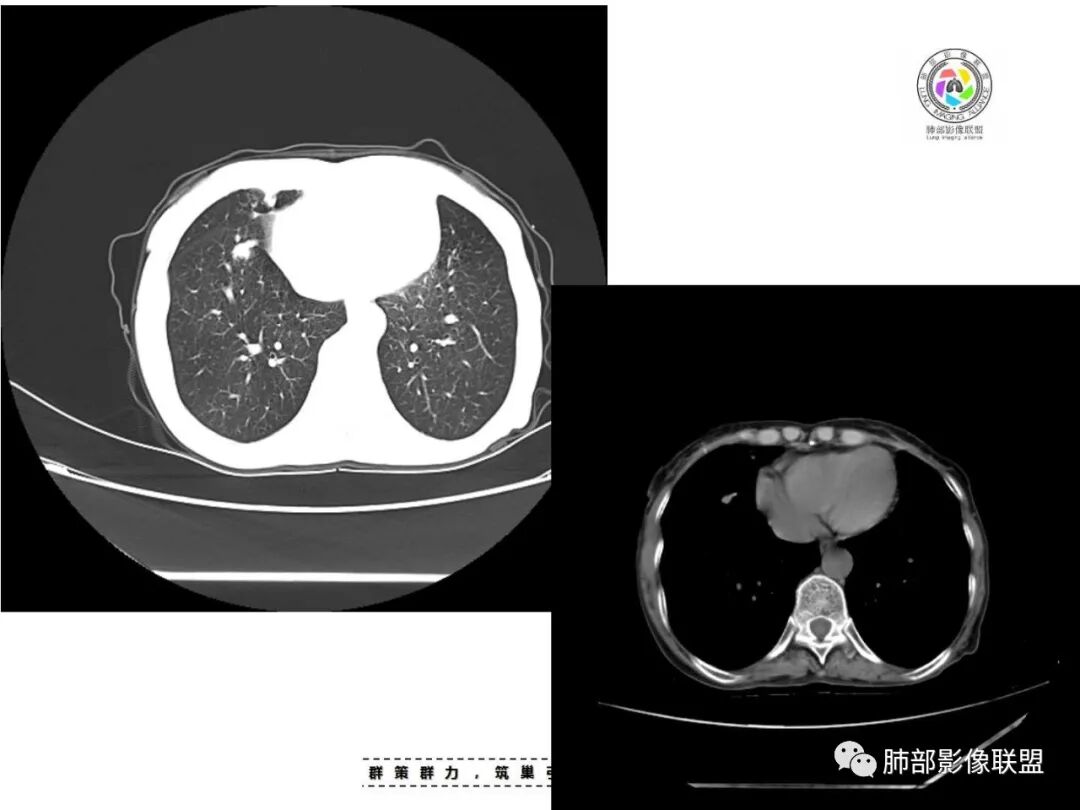

双肺多发片状影,索条影及小结节影,并见少许钙化,右肺上叶为主,主病灶无彭隆,考虑结核可能大

双肺不均匀散在分布斑片状,条索状,斑点状影,边缘部分清晰,可见部分病灶钙化,考虑感染性病变,结核?NTM?详细询问病史,尘肺+结核?

双上肺多发片状、索条影及小结节影,并见少许钙化,右肺上叶后段肿块,后段支气管阻塞,边缘膨隆,双上肺小叶间隔增厚呈多发结节状,胸膜局限性增厚,考虑:1、双肺上叶结核;2、右肺上叶后段腺癌并癌淋。

老年女性,短病程,咳嗽,咳痰为主诉,双肺多发病灶,右上为主,实变,小结节,条索,考虑结核,但小叶间隔增厚,胸膜下多发结节,警惕肿瘤。

女,67,咳嗽咳痰半月,双肺多发病灶,部分钙化,右肺为著,右肺上叶大片实变影,累及胸膜,右肺上叶支气管堵塞,右侧肺门略增大,考虑肺癌,双肺结核。

老年女性,主病灶在右肺上叶,有点散,周围可见卫星灶及少许树芽,双肺多发索条、结节及散在钙化,纵隔及肺门见钙化淋巴结,考虑结核。

双肺多发斑片,索条及结节影,内可见钙化,右肺上叶后段支气管截断,断端圆钝略扩张,双肺门及纵膈淋巴结钙化,双侧胸膜增厚伴钙化。首先考虑结核。右肺上叶亚段气管分叉处结节,警惕肿瘤

老年女性,双肺索条纤维影,右肺上叶散在卫星灶,树芽征,小叶中心融合,右肺后段支气管圆形截断,实变病灶内支气管扩张,考虑结核。

老年女性,病史半个月,两肺上叶为主病灶,多发不规则实变影、条索状影及散在小结节影,首先考虑结核,警惕合并肺癌,尤其是右肺上叶团块实变影。还可以看看重建图像,必要的增强。

患者老年女性,咳嗽、咳痰半月余。查体双肺可闻及痰鸣音。胸部CT:双肺上叶可见多发结节、条索、斑片实变影及小叶间隔增厚,部分见分叶、长毛刺及钙化,表面光滑,纵隔淋巴结有钙化。综合考虑良性病变,结核可能大,鉴别腺癌并癌性淋巴管炎。

老年女性,咳嗽咳痰,双肺散在片状及索条状高密度影,以右肺上叶为主,周围可见结节,实变内可见钙化,纵膈及双肺门可见钙化淋巴结,首先考虑感染性病变,结核可能大,警惕右肺上叶肿瘤并癌性淋巴管炎

双肺多发斑片,索条及结节影,内可见钙化,右肺上叶结节影,空泡,右肺上叶后段支气管截断,断端圆钝略扩张,双肺门及纵隔淋巴结钙化,双侧胸膜增厚伴钙化。首先结核肯定会有,右肺上叶结节,考虑腺癌

老年女性,咳嗽咳痰半月,肺部听诊痰鸣音。影像以右上肺实变?肿块?与支气管关系不清晰;另见两上肺结节、条索,胸膜局部增厚有钙化点,纵隔肺门淋巴结见钙化。综合考虑结核可能性大,注意肺癌。完善增强及支气管镜等检查。

老年女性,咳嗽咳痰半月,双上肺多发条索影,结节影,密度较高,右肺上叶不规则肿块,内有钙化,靠近胸膜下,靠内侧可见斑片影,树芽征,支气管壁增厚,考虑尘肺并肺结核,肺癌待排。

1.双肺片状影、大小不等斑片影、结节影、树芽等,病灶密度偏高多钙化。

2.病灶上肺为主,胸膜下分布为主。双肺病灶明显不对称,右肺块状影较大。

3.纤维条索影广泛杂乱、牵拉,横向分布为主,这点给人也印象很深!

4.纵隔轻度右移。双肺门纵隔淋巴结增大钙化。

5.老年女性患者,咳嗽咳痰半月余